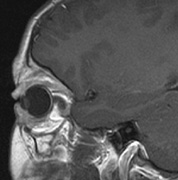

The eyelids are frequently involved in NF1. The lateral portion of the upper lid is prone to develop a plexiform neurofibroma, producing a sinusoidal or S-shaped deformity of the lid margin.54–56 Amblyopia develops from ptosis and astigmatism (Fig. 4).

|

Optic nerve gliomas may involve the optic chiasm and be associated with endocrine disorders or nystagmus.68–70 Surgical excision of chiasmal gliomas (Fig. 6) carries a high risk of visual loss. Invasion of the hypothalamus or the third ventricle carries a poor prognosis, with greater than 50% 15-year mortality rate.71 One review of radiation treatment for chiasmal gliomas collated data from small case series and found no significant long-term improvement in visual function, progression, or mortality with radiation treatment.71 Other reports suggest that radiation doses over 4500cGy improve symptoms and slow progression of chiasmal gliomas over several years.72 Adequate tumor coverage by radiotherapy results in irradiation of normal brain and nearly all children need hormone replacement.73 Chemotherapy is an alternative.74,75